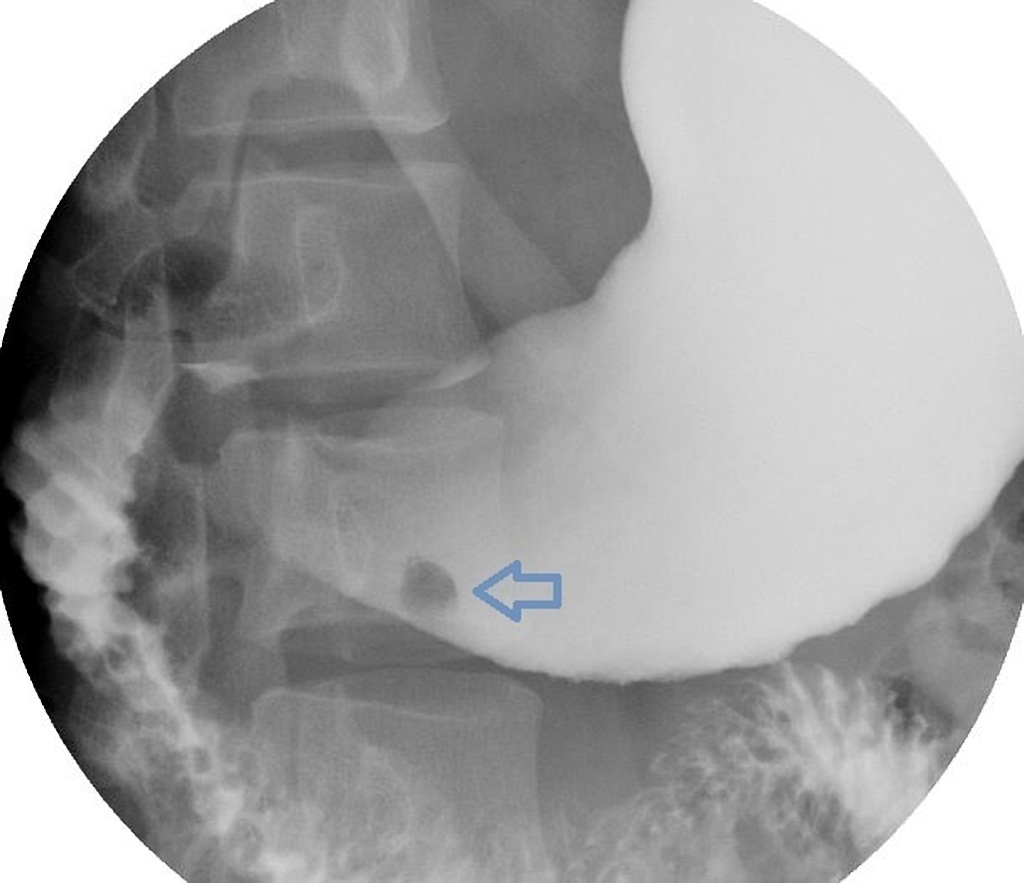

stomach ulcer

A small ‘pit’ of barium contained within an ulcer cavity in the body of the stomach: Bull’s eye sign